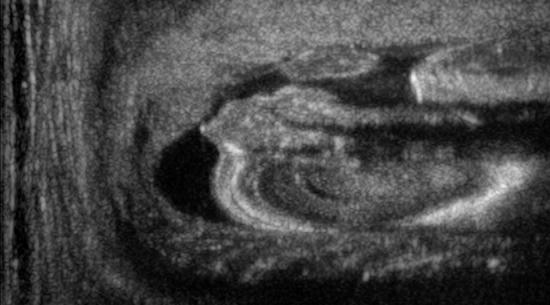

We train each learning-based network (custom-WDSR) with 1.5K images, where the input is the outcome of the selected up-sampling method (i.e., Cubic convolution), and the target is the original high-resolution image. Indeed, input and target images have the same resolution, as the reconstruction of the missing lines has been already performed by Cubic convolution. Figs. 3, 4, and 5 show the results of the network prediction, compared with the input and the target images. Target images correspond to spatial high-resolution images; input images are the outcome of the up-sampling interpolation, which is applied to spatial low-resolution images (i.e., the down-sampling along the lateral direction of high-resolution images); prediction images represent the output of the neural network.

Our framework visually improves the results, in terms of blurring and artefacts. This result is more evident in the magnification of the ear of the foetus (Fig. 3), the mitral valve (Fig. 4), and the mass edges (Fig. 5). Fig. 6 shows the error image of the three anatomical districts with both 2X and 4X up-sampling factors, with the maximum error in the scale . The error is more evident in the contours of the anatomical structures; moreover, the abdominal district shows a smaller error than the cardiac and obstetric ones. We underline that the view for each image is scaled to its maximum, to improve the visualisation of the error.